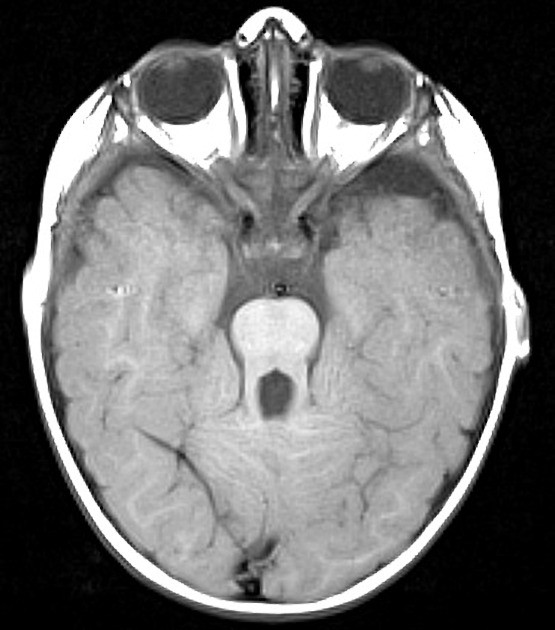

Case 1 cranial MRI showing "molar tooth sign" (arrows), which is a... Download Scientific Diagram What Is Molar Tooth Sign Find out how to diagnose. learn about the common causes of molar tooth pain, such as cavities, gum disease, infections, and sinusitis. learn about the signs and complications of impacted wisdom teeth, the third molars that don't have enough room to emerge or develop in the mouth. joubert syndrome is a condition that causes the molar tooth. What Is Molar Tooth Sign.

Molar tooth sign (arrow) in axial RMI images, for a patient with... Download Scientific Diagram What Is Molar Tooth Sign learn about the common causes of molar tooth pain, such as cavities, gum disease, infections, and sinusitis. learn about the different causes of molar tooth pain, such as cavities, abscesses, impacted wisdom teeth, and sinus infections. learn about the function, types, and eruption of molars, the flat teeth in the back of the mouth used for grinding. What Is Molar Tooth Sign.

.Molar tooth sign Joubert syndromeis an autosomal recessive disorder characterized by abnormal